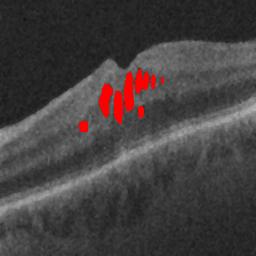

The qualitative results of the proposed system is shown in the Fig. 3. The detection task is evaluated using Area Under the Curve(AUC) metric and the segmentation task is evaluated using Dice Coefficient(DC) metric and the results are presented in Table1

| (a) De-noised OCT slice | (b)Predicted fluid region | (c)Manual fluid segmentation |

|

|

|

| (d) De-noised OCT slice | (e)Predicted fluid region | (f)Manual fluid segmentation |